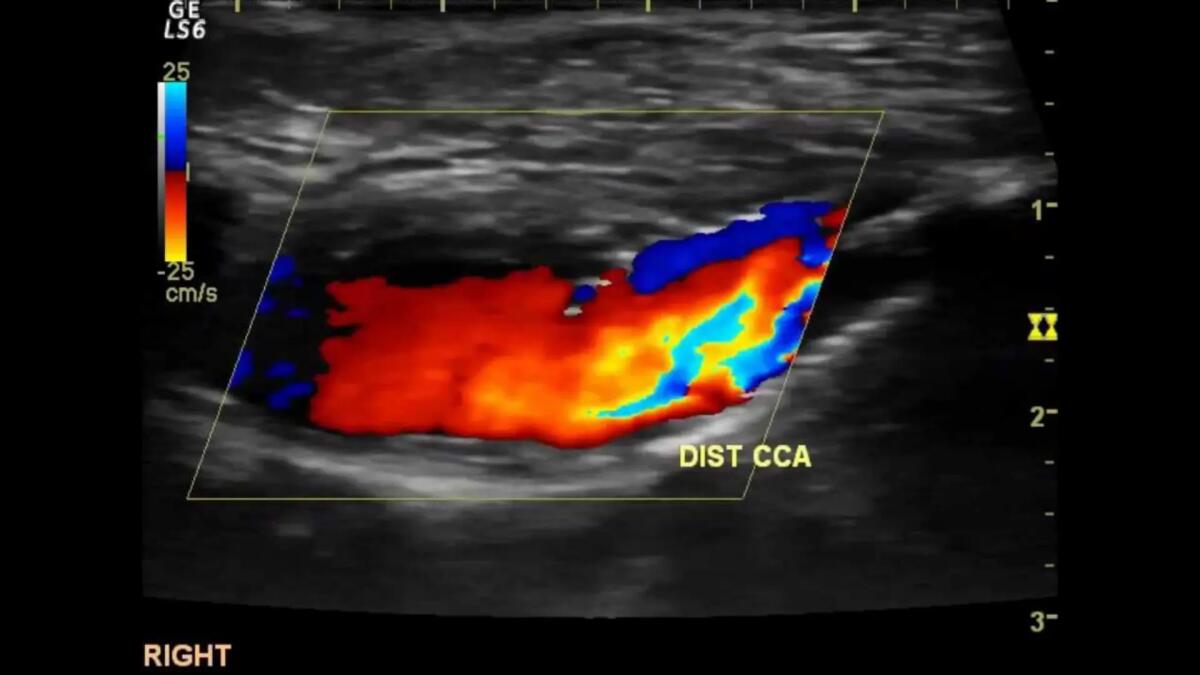

Sabato 14 ottobre negli ospedali di San Donà, Portogruaro e Jesolo scatterà il “Doppler day” ossia una giornata di doppler a ciclo continuo con lo scopo di ridurre le liste d’attesa per questa diagnostica.

Gli ambulatori attivati appositamente per questa iniziativa saranno complessivamente 9, nei tre ospedali dell’Ulss 4, all’interno dei quali 12 medici e 12 infermieri effettueranno ecocolordoppler dei tronchi sovraortici ed ecocolordoppler venoso degli arti inferiori.

“E’ un’attività a carattere straordinario, attivata nei tre ospedali per consentire all’utenza di recarsi nel presidio più vicino a casa – spiega il direttore generale dell’Ulss4, Mauro Filippi -. Dalle ore 8.00 alle 16.00 verranno effettuati complessivamente 200 ecodoppler: un contributo importante nella riduzione dei tempi d’attesa”